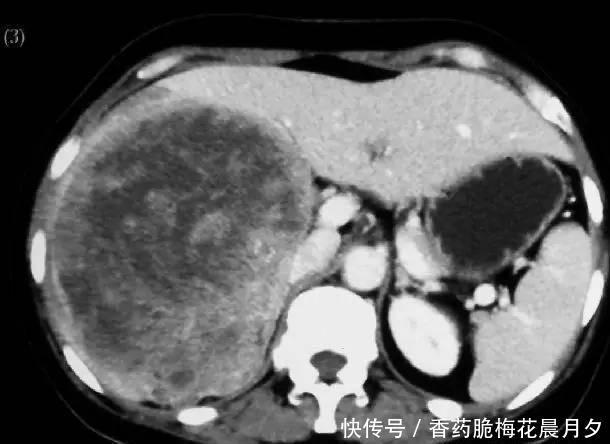

文章图片

反映肝脏好坏,临床用的最多的的影像检查就是超声。当然CT、MRI等检查也是发现肝脏不好的影像检查。对人体危害最危险的疾病:肝癌往往是通过超声筛查出来。脂肪肝、肝硬化的严重程度等也是可以通过超声等影像检查出来的。